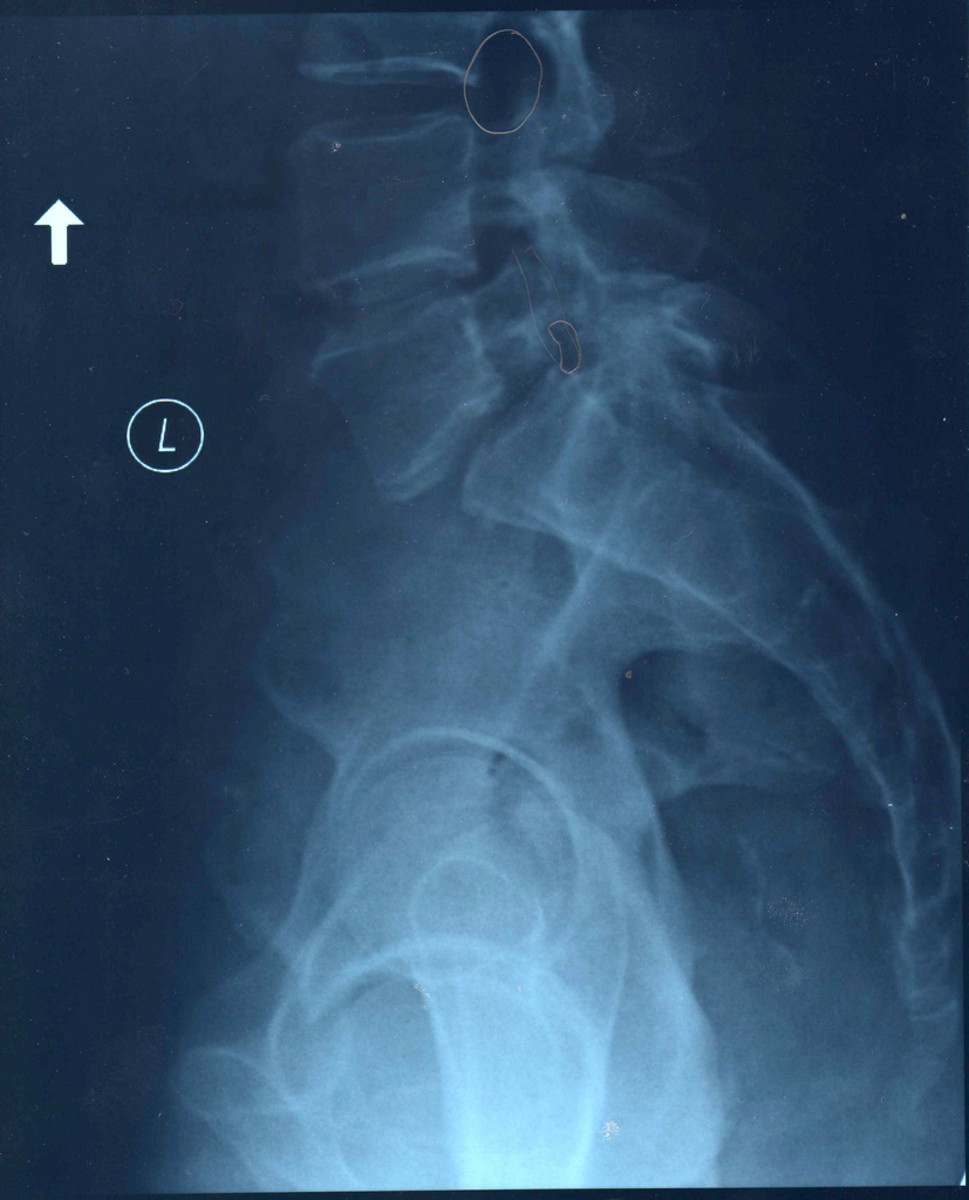

mri procedures and pathology lumbar spondylolisthesis

From mriproceduresandpathology.blogspot.com

mri procedures and pathology lumbar spondylolisthesis Lumbar Spondylosis And Sciatica Spondylosis is a broad term describing spinal degeneration and pain, often associated with osteoarthritis of the spine. These changes are often called. It is also known as spinal osteoarthritis. Spondylosis can occur in the cervical spine (neck), thoracic spine (upper and mid back), or lumbar spine (low back). Spondylosis is a degenerative condition of the spine and usually involves the. Lumbar Spondylosis And Sciatica.